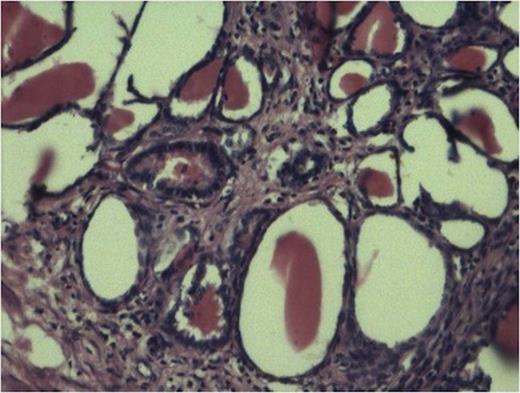

The sections from various representative areas revealed dilated pelvicalyceal system lined by metaplastic squamous epithelium and shows changes of chronic pyelonephritis (Fig 2).

Cyst lined by metaplastic epithelium with focus of malignant squamous cell. (100x H and E stain)